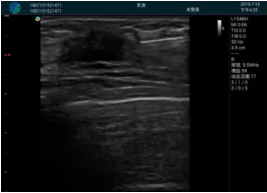

可視化穿刺引導(dǎo)

M20實(shí)時引導(dǎo):向包塊后方間隙注射利多卡因

清晰顯示腺體內(nèi)低回聲快影,邊界清晰,包膜較光滑

確定進(jìn)針路徑并實(shí)時監(jiān)測抽吸針與腫塊位置關(guān)系

抽吸針進(jìn)入腫塊內(nèi)部進(jìn)行旋切

抽吸過程中可見腫塊明顯縮小,并根據(jù)腫塊位置改變針道位置

抽吸旋切后再進(jìn)行超聲復(fù)查,原腫塊區(qū)域未見殘留組織及出血

超聲引導(dǎo)下抽吸旋切取出的腫塊組織